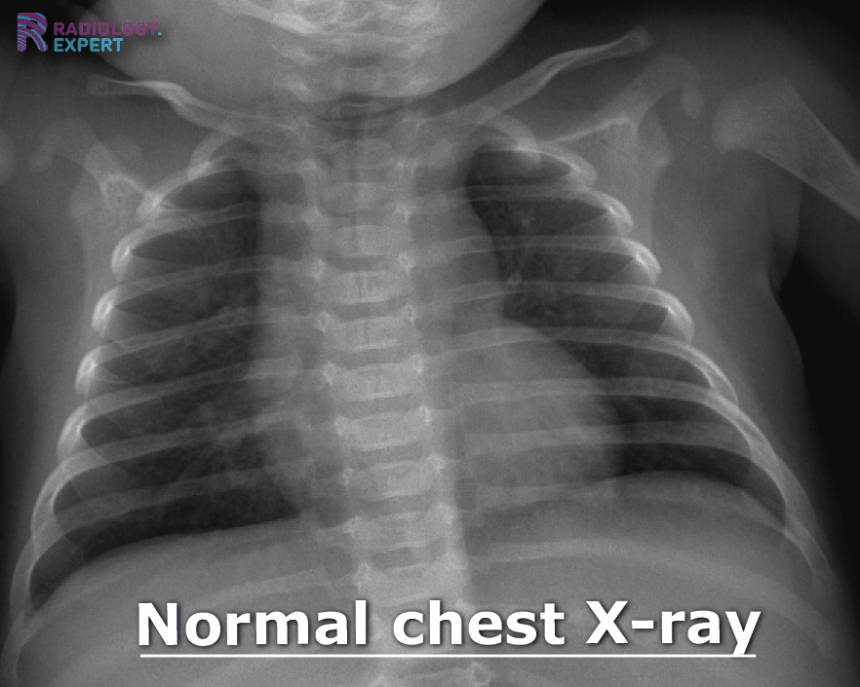

From www.radiology.expert

Chest Xray child Pediatric Chest X Ray Cpt Code 72191 73206 73706 74175 74174 75635. Depending on the patients' age,. The final impression noted diffuse lung. The current procedural terminology (cpt ®) code 71101 as maintained by american medical association, is a medical procedural code under. You should not report 71020 (radiologic examination, chest, two views, frontal and lateral) in this case because cpt. The chest radiograph is one. Pediatric Chest X Ray Cpt Code.